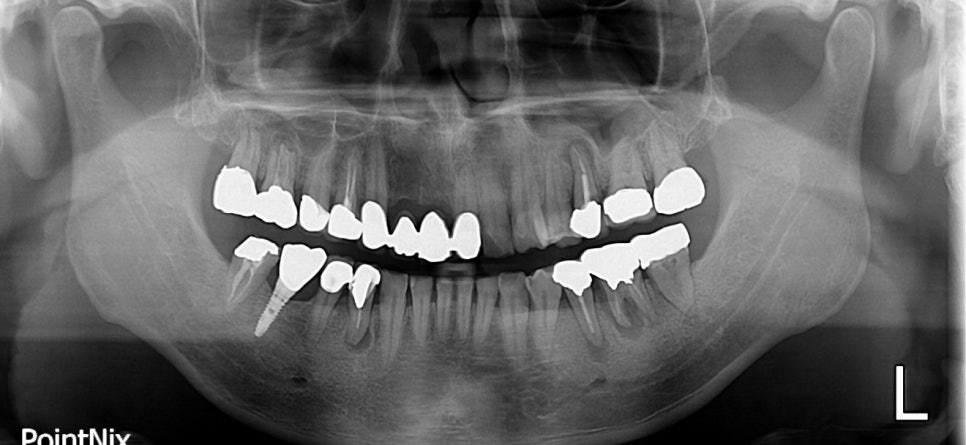

당뇨병 환자로 치주염을 앓고 있을 때의 X-RAY

당뇨질환을 가지고 계신 분 중 치주염을 앓고 계신 경우가 상당히 많습니다. 이러한 원인은 당뇨로 인해 면역기능이 약화되어 세균 감염의 위험이 일반 경우보다 높습니다. 당뇨병의 여러 합병증 중에 잇몸병은 6번째 정도 흔한 합병증이며,

특히 혈당이 조절되지 않을 경우에는 잇몸병의 진행이 매우 빨라져 위험합니다.